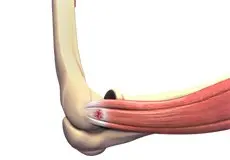

Tennis Elbow

Tennis elbow is a common name for the elbow condition lateral epicondylitis. It is an overuse injury that causes inflammation and microtears of the tendons that attach to the lateral epicondyle.

Golfer's Elbow

Golfer’s elbow, also called medial epicondylitis, is a painful condition occurring from repeated muscle contractions in the forearm that leads to inflammation and microtears